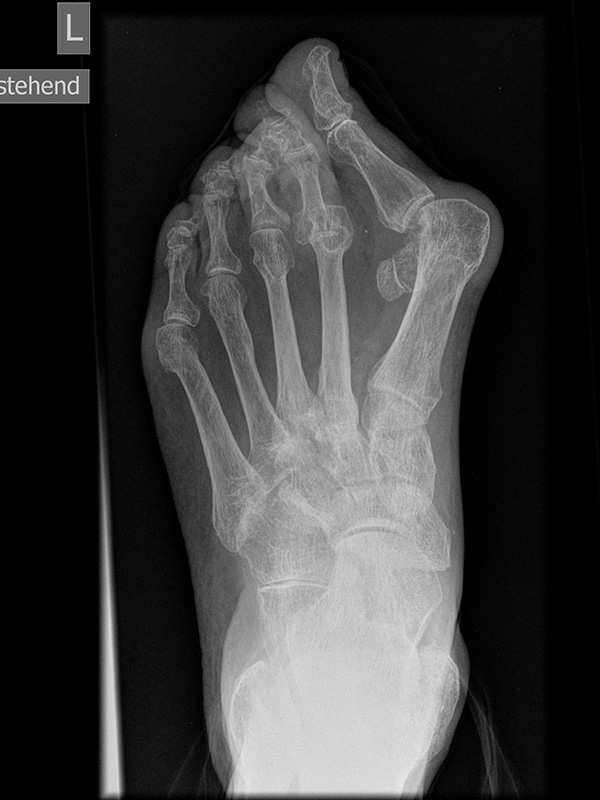

Fuß dp (dorsoplantar) mit Belastung

Positionierung:

• Der Patient steht unter gleichmäßiger Gewichtsbelastung auf beiden Füßen.

• Die Fußachse ist nach vorne gerichtet.

• Die Kassette liegt unter dem zu röntgenden Fuß.

• Der Zentralstrahl wird auf das Tarsometatarsalgelenk II zentriert.

• Die Röntgenröhre ist 15° vertikal gekippt.

• Anmerkung: Technisch lässt sich die Röhre beim stehenden Patienten nicht in 0° über dem Fuß positionieren. Eine Kippung der Röhre um 15° erlaubt darüber hinaus eine bessere Einsicht in die tarsometatarsalen Gelenke.

Kennzeichen des Röntgenbildes:

• Standardabbildung des Fußes zusammen mit der belasteten seitlichen Aufnahme und der unbelasteten Schrägaufnahme.

• Die belasteten Aufnahmen liefern relevante Informationen zur Fußstatik und sind die Grundlage aller achskorrigierenden Eingriffe an Vor- und Rückfuß.

• Sämtliche Winkelbestimmungen beziehen sich auf belastete Aufnahmen.

Besondere Bemerkungen zum Beispielbild:

• Schwere Hallux valgus Deformität.

• Die Sesambeine sind luxiert, ebenso das Großzehengrundgelenk. Luxation des Metatarsophalangealgelenks II.

• Degenerative Veränderungen der tarsometatarsalen (TMT) Gelenkreihe, betont TMT II und III.